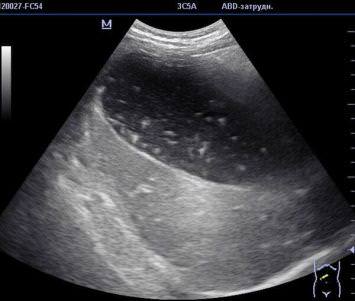

Патология выражена признаками диспепсии, не имеет стандартного очага. Характерные перегибы желчного пузыря провоцируют перетяжение тела с последующим риском его разрыва. Боль имеет неопределенную локализацию, необходимо проведение УЗИ для определения пораженного участка. Если здоровый орган имеет вид мешка, то пораженный – приобретает очертания бумеранга, песочных часов, грушевидную форму. Сначала болевой синдром выражен слабо, но со временем становится интенсивным, и действие анальгетиков уже не способно продлить период ремиссии.

Диагностика загиба

Диагностировать загиб несложно. Наиболее информативным методом диагностики патологии является ультразвуковое исследование. Оно позволяет не только выявить патологию, но и определить функциональное состояние органа, точную локализацию загиба, а также оценить анатомические особенности стенок, шейки, тела.

Определить причину патологии сложнее. Для дифференциации врожденного заболевания от приобретенного ультразвуковое исследование желчного проводится дважды: на голодный желудок и после употребления яичных желтков, которые вызывают повышенное выделение желчи. Когда перегиб пузыря является врожденной патологией, деформация органа остается без изменений.

В рамках инструментальной диагностики назначают ультразвуковое исследование.

- Обследование проводят натощак.

- Обследование проводят спустя полчаса после приема медикаментов, активизирующих синтез желчи, или продуктов, обладающих подобным действием. Диагност может определить тип патологии – при фиксированной деформации изменения отсутствуют, в случае приобретенного загиба орган уменьшится.

Степень перегиба органа, депонирующего желчь, определяет вероятность развития его дисфункции, возможных сопровождающих заболеваний, а также скорость наступления этих последствий и их динамику. Встречаются изгибы различной конфигурации, единичные, множественные. В результате желчный пузырь на мониторе аппарата УЗИ проявляется удивительными формами, например:

Известно, что в группе обратившихся за медицинской помощью в связи с болезнями билиарной системы перегиб диагностируется методом УЗИ примерно у 30% пациентов.